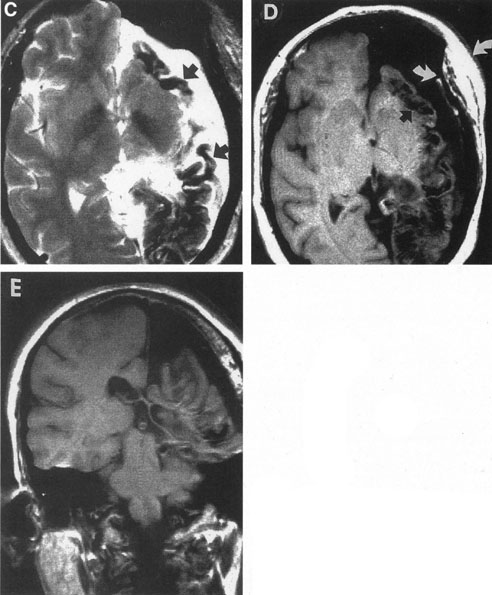

In some persons, the cavernous sinuses have existing or potential connections to the deep venous system of the brain. Indeed, this may be the preferential route of venous drainage from all or part of the cavernous basal sinus complex. Therefore, the clinical appearance of orbital venous hypertension associated with a cavernous dAVM may be relatively minimal, but arterialized flow is transmitted instead chiefly via venous dural channels draining the medial aspects of the temporal lobes and the basal vein of Rosenthal. The latter drains an extensive deep parenchymal territory, including part of the posterior fossa. This effluent pattern explains how some cavernous dAVMs or CCFs present with relatively minor outward physical signs but with serious complications from cortical venous hypertension (Fig. 18), elevated intracranial pressure (a form of secondary pseudotumor cerebri syndrome; see Chapter 5, Part II), temporal lobe seizures, brain parenchymal hemorrhage caused by venous infarction or venous rupture (Fig. 19), or edema of the posterior fossa structures.119

Fig. 18. A 25-year-old man developed severe right-sided proptosis and a loud bruit at the time of a vehicular accident. Lateral projection of the right internal carotid artery in the early arterial phase (A) and late arterial phase (B) in anteroposterior projection demonstrate immediate opacification of the superior and inferior ophthalmic veins (straight arrows), the inferior petrosal sinuses (curved arrows) and of the deep parenchymal veins of the right hemisphere (open curved arrows). The fistula was related to a large carotid laceration involving the cavernous and supraclinoid segments of the right internal carotid artery. The artery could not be preserved at the time of treatment. C: Latex balloons (open-ended arrowheads) were placed in the fistula and within the carotid artery at the time of treatment. (Courtesy of Frank Huang-Hellinger)

Fig. 19. A 30-year-old woman presented with headaches. Lateral views of left (A) and right (B) internal carotid arteriograms demonstrate developmental venous malformation of the cribriform plate supplied by both ophthalmic arteries. Note subarachnoid veins of the anterior cranial fossa (curved arrows). In addition, the right ophthalmic artery (B) has a cavernous origin (arrow), a vestige of the dorsal ophthalmic artery that usually atrophies in fetal development.